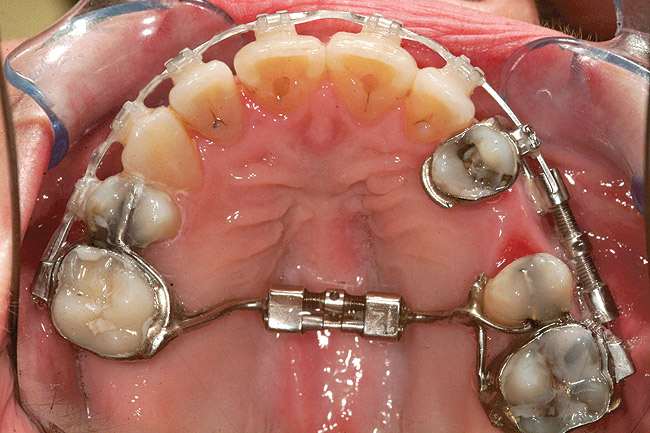

Fig 24 (through Fig 26). A 50-year-old female concerned about appearance and bite. Jackscrew appliance was placed after 6 months of orthodontic alignment.

Figure 24

Fig 25. A 50-year-old female concerned about appearance and bite. Jackscrew appliance was placed after 6 months of orthodontic alignment.

Figure 25

Fig 26. A 50-year-old female concerned about appearance and bite. Jackscrew appliance was placed after 6 months of orthodontic alignment.

Figure 26

Fig 27. Patient was missing tooth No. 11 and had A-P and transverse maxillary deficiencies with anterior and left posterior crossbites. Bite was opened with glass ionomer cement. Single-tooth osteotomies were performed on teeth Nos. 6 and 12 and multiple-tooth osteotomies were completed on teeth Nos. 3 to 4, 7 to 10, and 13 to 14.

Figure 27

Fig 28. Corticotomies were also performed on Nos. 7 to 10 segment. Postsurgery 21 days.

Figure 28